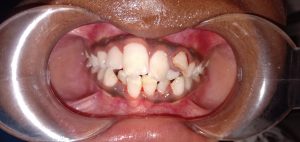

We at the Department of Pediatric & Preventive Dentistry focus on comprehensive oral health care needs of a child from infancy to adulthood and provide comprehensive, therapeutic as well as preventive care to all children including those with special care needs.

- Proposed a modification of Angle’s classification for application in primary dentition and various cross sectional studies have been carried out to validate its application.

Treatment and Services